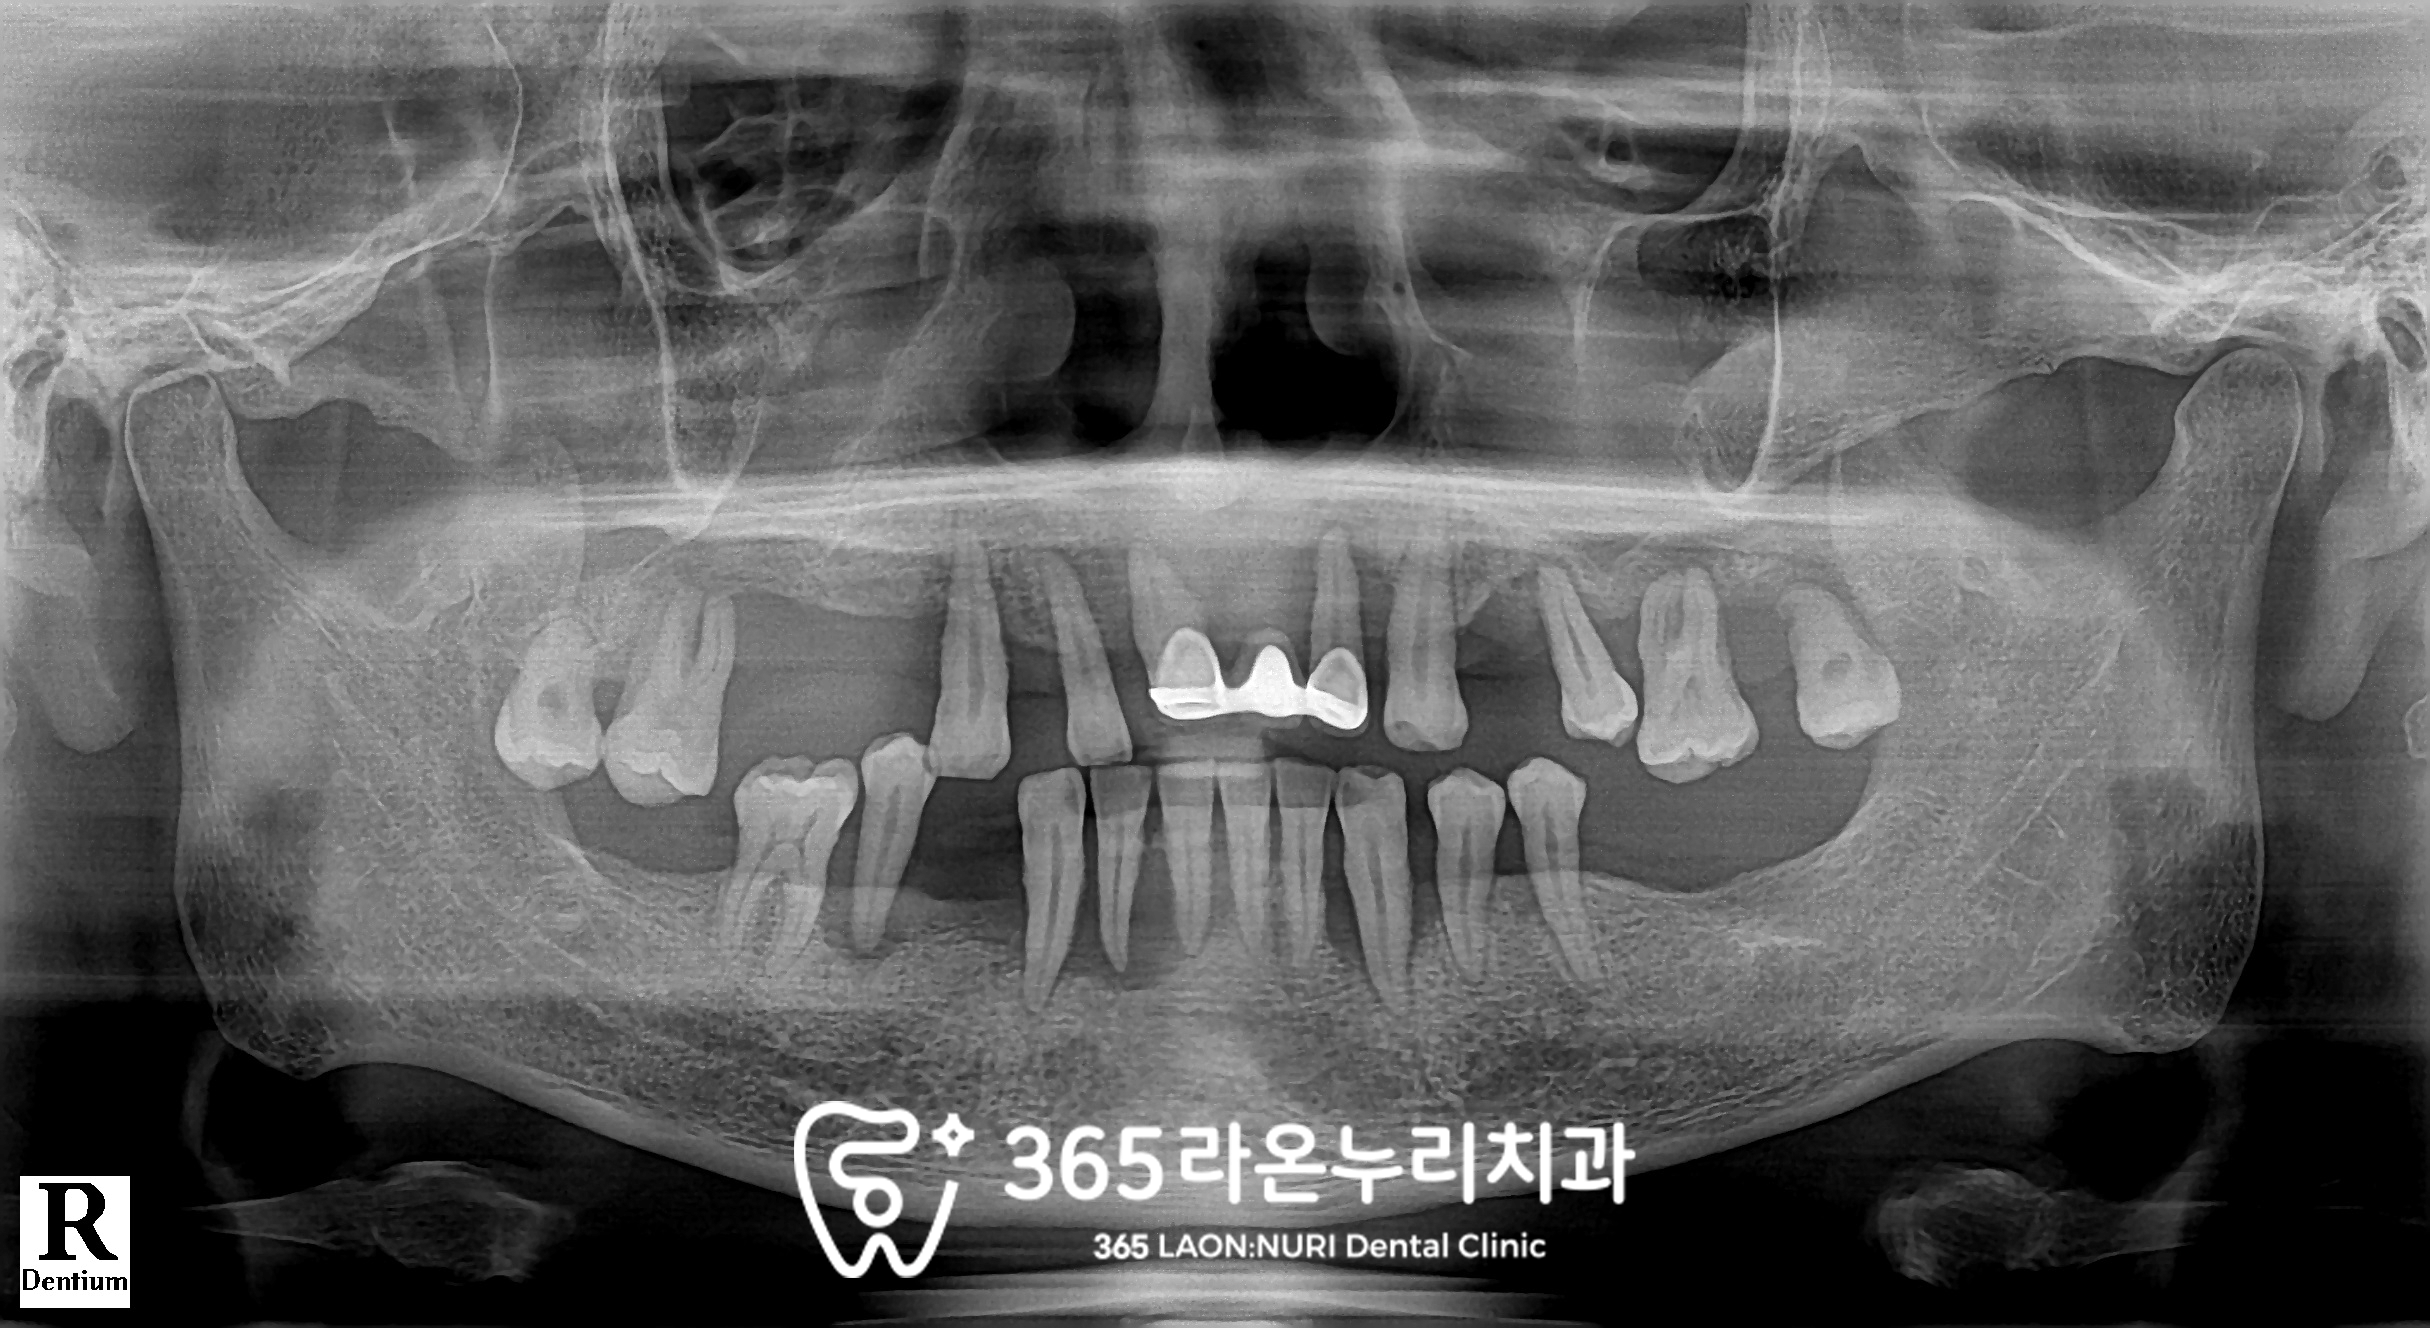

파노라마를 찍게 되는데

이 과정에서 치조골의 높이와

치아 뿌리 끝 염증까지 확인할 수 있습니다.

엑스레이를 통해 살펴보니

치조골의 높이가 상당히 낮아져있으며

위아래가 제대로 물리는 곳이 없을 만큼

교합도 불안정합니다.